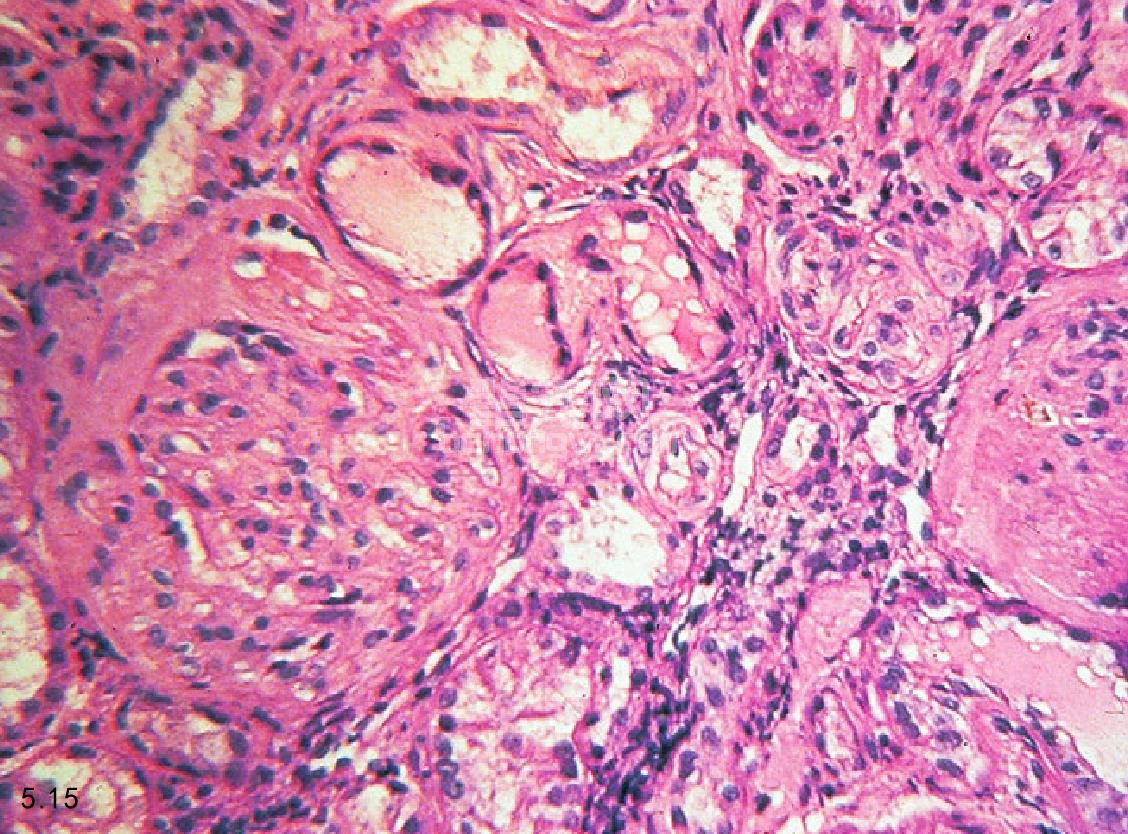

图5.15和图5.16 犬慢性肾衰竭肾脏的组织病理学。图5.15肾血管球硬化症和单核性间隙性渗透病变。图5.16肾小管萎缩和间隙纤维化。